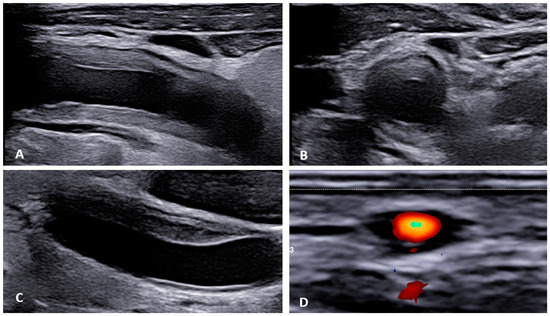

Takayasu’s arteritis (TA) is a rare chronic inflammatory granulomatous disease of larger vessels, such as the aorta and its branches [36]. Its origin remains unclear, and patients are primarily young females (<40 years) and children [37]. TA exhibits unspecific clinical symptoms, such as fever, joint tenderness, and headaches, as well as specific vascular symptoms, including Raynaud’s syndrome, syncopes, or erythema nodosum [37]. Moreover, CV complications such as myocardial infarction, stroke, or peripheral artery disease are not uncommon [37]. Imaging of large vessels is paramount for the diagnosis of TA (Figure 2A,B).

Giant cell arteritis (GCA) affects typically large- and medium-sized arteries, including the carotid arteries and their extracranial branches, as well as the aorta and its branches [48]. Symptoms of GCA include headache, jaw claudication, tenderness of the temporal artery, and low-grade fever [49]. Typical complications of GCA include acute loss of vision and aortic aneurysms, which in turn can lead to more severe complications like stroke or aortic dissection [49,50]. GCA is frequently linked with polymyalgia rheumatica (PMR), characterized by muscle pain and bilateral morning stiffness in the proximal extremities. At a microscopic level, giant cells infiltrate the vascular wall, leading to an occlusion of the affected blood vessels and thus to ischemia of the tissue to be supplied [51]. The diagnosis of PMR/GCA is usually based on clinical presentation, imaging, temporal artery biopsy (Figure 2C,D, Figure 3 and Figure 4), and the ACR/EULAR classification criteria [49,52].

Figure 2. Ultrasonographic findings in patients with large vessel vasculitis: (A,B): B-mode US with the finding of concentric carotid intima-media thickening in a patient with Takayasu’s arteritis ((A) longitudinal plane, (B) transversal plane). (C). B-mode US: carotid intima-media thickening in a patient with giant cell arteritis. (D): Power Doppler US in a patient with temporal arteritis (typical “HALO” sign). Courtesy of Dr. Konstantinos Triantafyllias, Rheumatology Center, Rhineland-Palatinate.